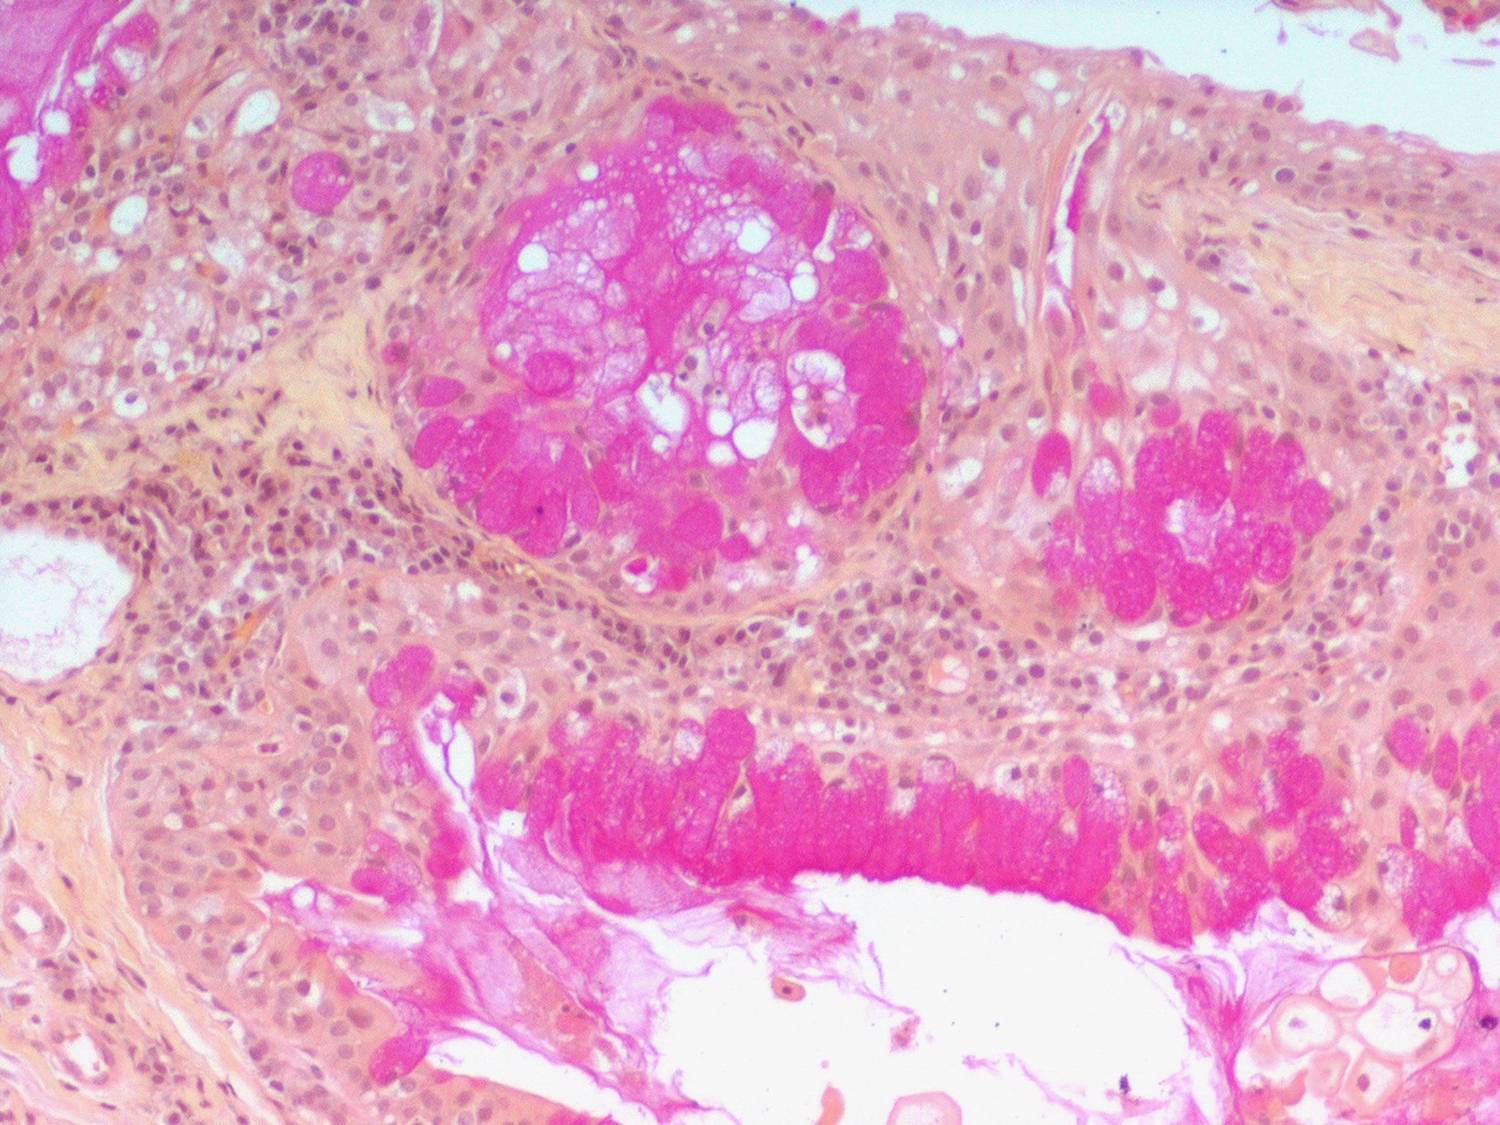

Mucoepidermoid carcinoma =الكارسينوما المخاطية البشروانية